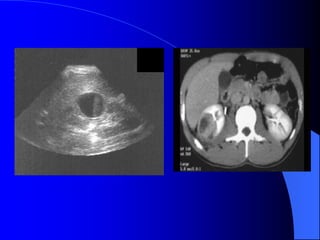

3.3. Nang caûnh bãø tháûn

Täøn thæång laình tênh

Xaøy ra åí moüi læïa tuäøi

Thæåìng khäng coï triãûu chæïng, træì khi

nang låïn cheìn vaìo bãø tháûn gáy âau læng,

cheìn vaìo âäüng maûch tháûn gáy tàng huyãút aïp.

Nang hçnh thaình do âæåìng baûch maûch

giaîn. Nang chæïa dëch coï albumine, lipide vaì

cholesterole.

Nang thæåìng nhiãöu äø khäng thäng våïi

ÂBT, âáøy bãø tháûn vãö mäüt phêa hoàûc bao

quanh caïc ÂBT vaì keïo daìi caïc âaìi tháûn.

Trãn NÂTM coï thãø tháúy ÂBT bë âeì

âáøy.

Trãn siãu ám laì khäúi räùng ám, tàng

ám sau, thaình moíng, åí xoang tháûn.

Phán biãût våïi æï næåïc âaìi bãø tháûn, åí âáy

caïc nang caûnh bãø tháûn khäng thäng

nhau.

Nang cạnh bể thận